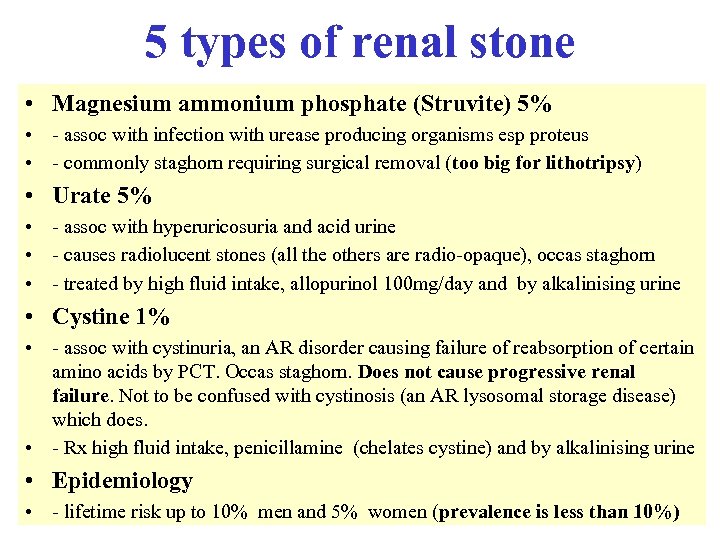

Reduced serum complement • • Occurs in: - SLE - infective endocarditis - post strep nephritis - shunt nephritis - cholesterol embolism - cryoglobulinaemia - MCGN types 1 and 2 • • Complement normal in FSGS, amyloidosis, Alports, anti GBM disease C 3 nephritic factor is an Ig. G auto antibody to the C 3 convertase of the alternative pathway of complement activation, found in both types of MCGN